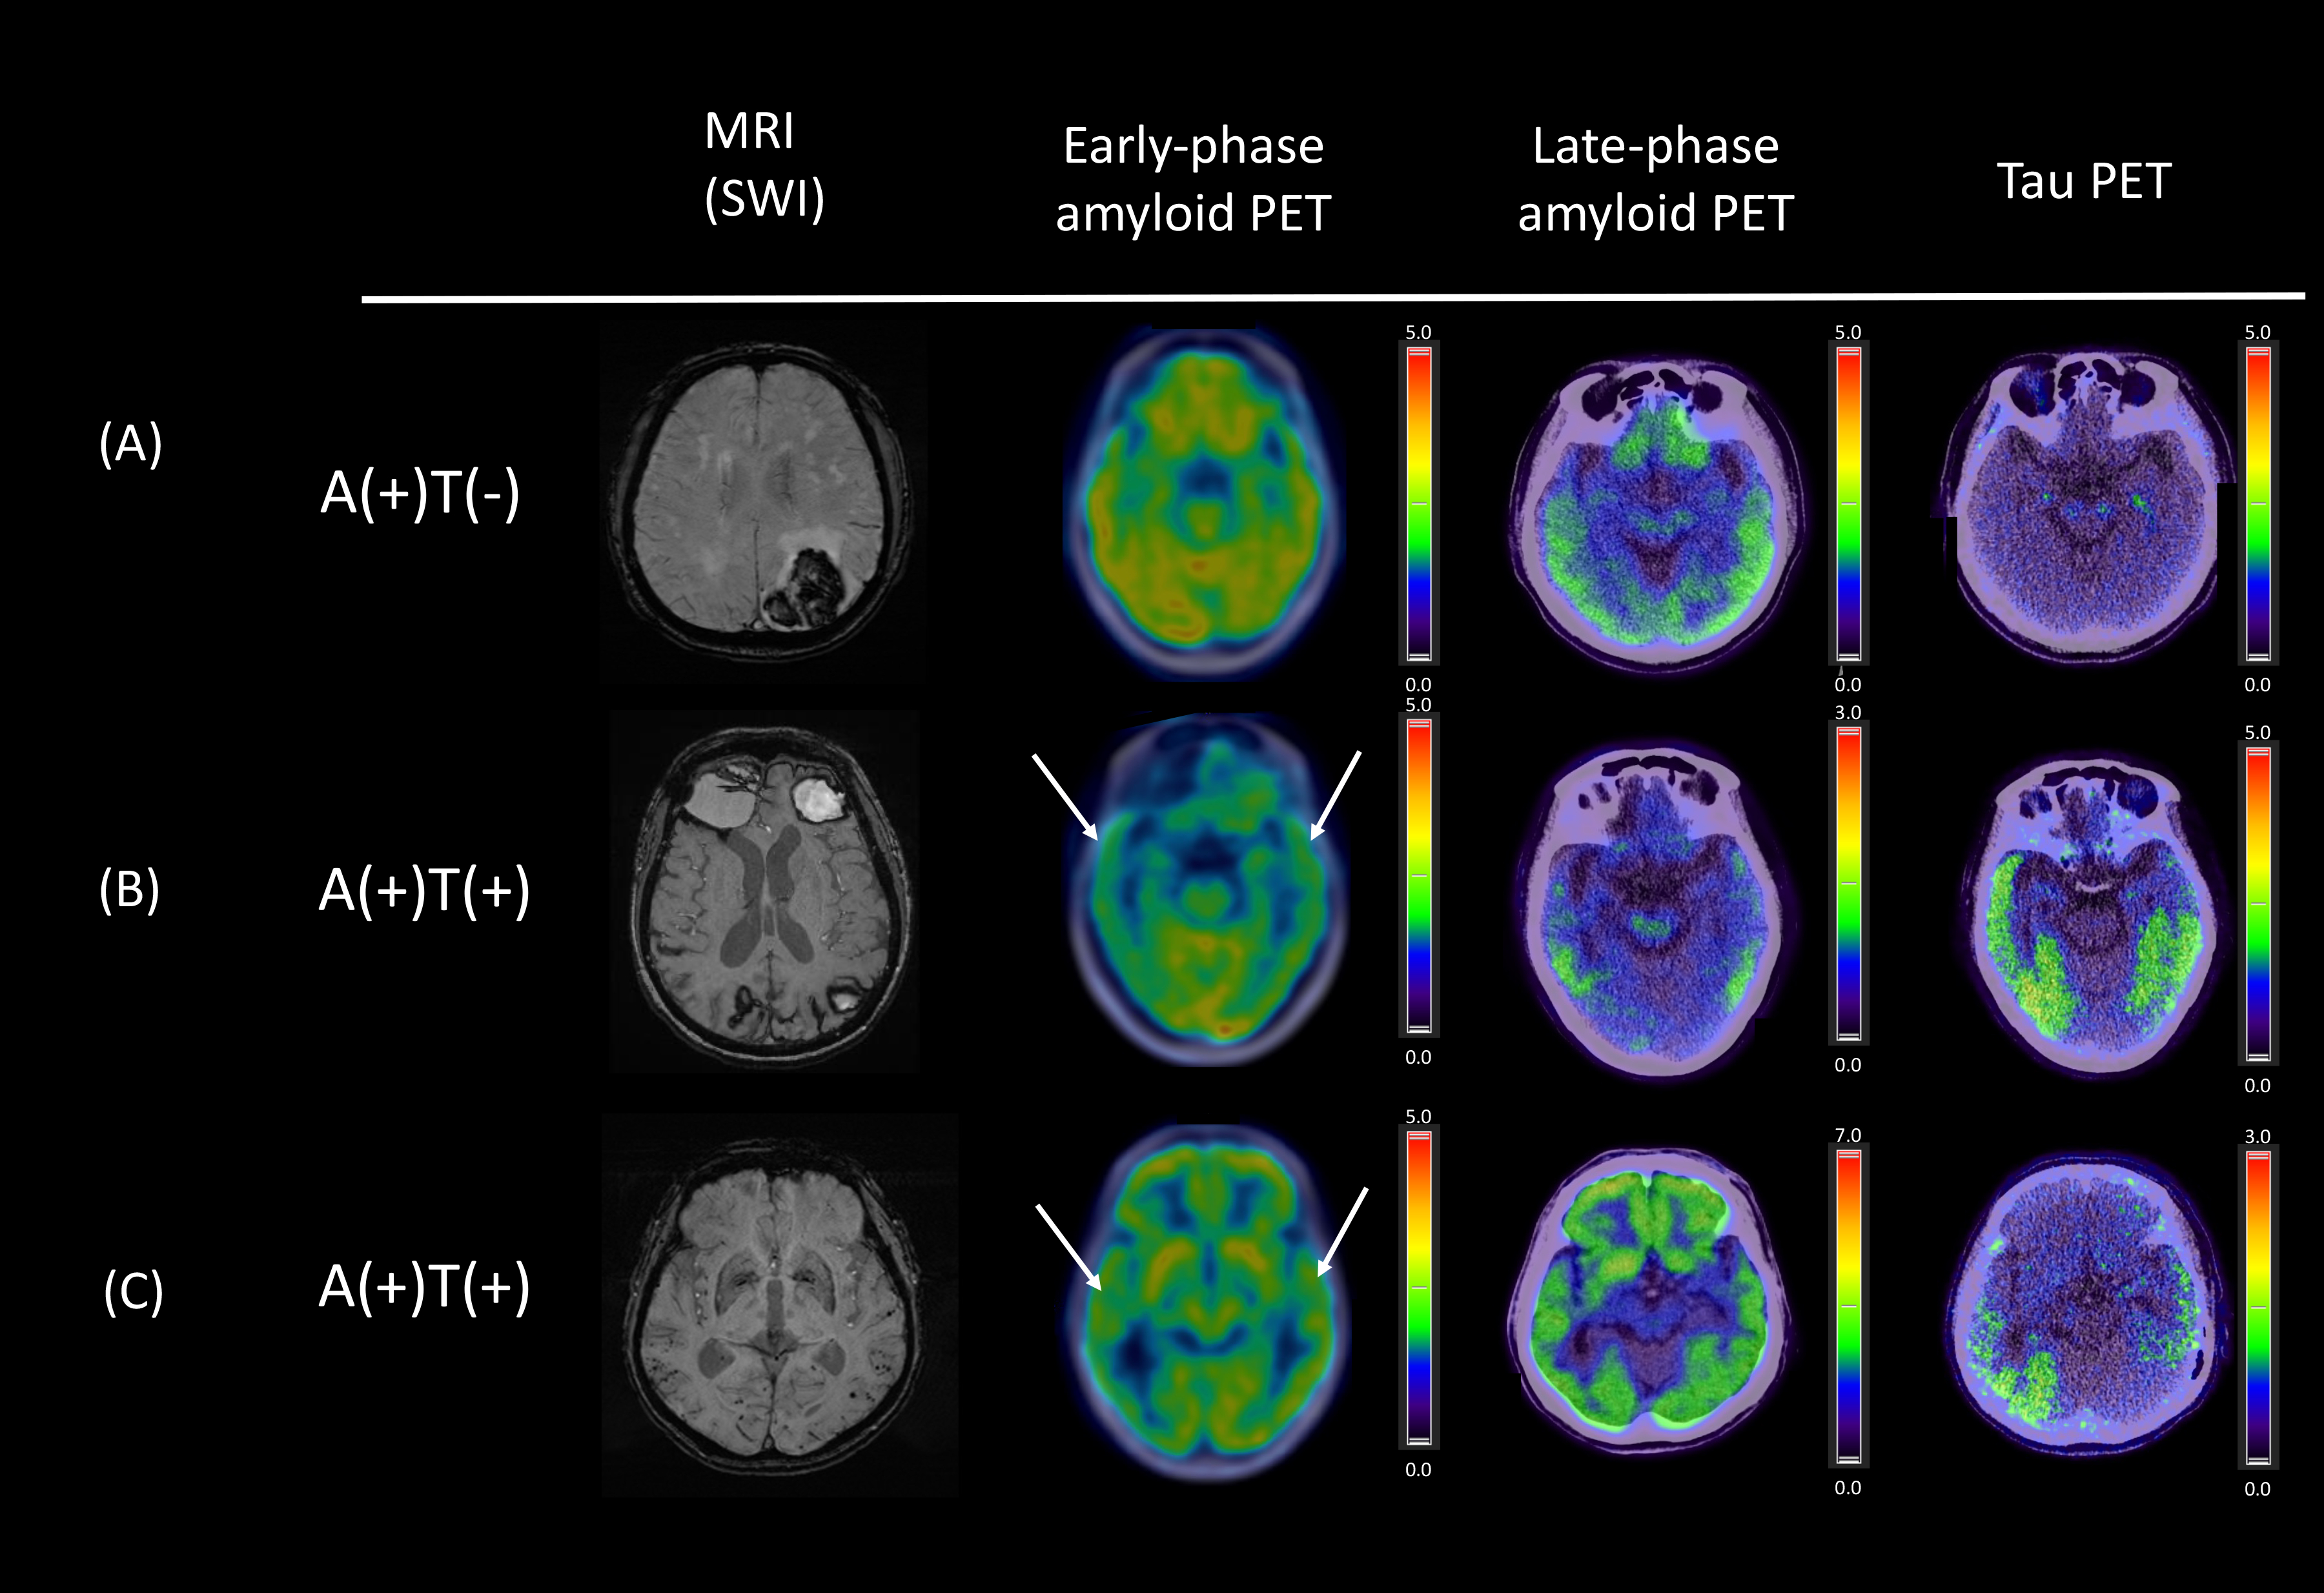

Abstract Body: Background and Objective: Cerebral amyloid angiopathy (CAA) is a major cause of lobar intracerebral hemorrhage and cognitive dysfunction in the elderly, and frequently coexists with Alzheimer’s disease (AD) and tau pathology. Dual-phase 11C-PiB PET can determine amyloid deposition and cerebral perfusion changes, and may have diagnostic value for detecting tau in CAA. This study aimed to assess the diagnostic utility of combining early- and late-phase PiB PET images in predicting tau pathology in CAA.

Methods: We prospectively enrolled patients with probable CAA for dynamic PiB and AV1451 scans. Tau positivity was defined as a standardized uptake value ratio (SUVR) > 1.26 in the meta-temporal region on static AV1451 PET. We compared early-stage (0-6 minutes after tracer injection) and late-phase (40-70 minutes) PiB PET between the tau(+) and tau(-) groups. Relationships between PiB PET parameters and tau burden were assessed using a linear regression model. Receiver operating characteristic (ROC) analysis was performed to evaluate the diagnostic value of PET parameters.

Results: No significant differences in age, sex, educational years, ApoE2 or ApoE4 carrier status were observed between the CAA/tau(+) vs. CAA/tau(-) groups. As expected, the CAA/tau(+) group had lower MMSE scores (p=0.021) and was associated with a lower hippocampal volume (p=0.036). On PET analysis, CAA/tau(+) was associated with lower early-phase temporal lobe PiB uptake than CAA/tau(-) (SUVR 0.87 [0.81-0.93] vs. 0.92 [0.89-0.98], p=0.014) and higher late-phase PiB uptake in the whole cortex and temporal and parietal lobes (all p<0.05). Early-phase temporal lobe PiB SUVR significantly correlated with tau burden (r=-0.34, p=0.038). Using Youden’s cutoff, early-phase temporal lobe SUVR had a sensitivity of 55% and specificity of 85% and late-phase temporal lobe SUVR had a sensitivity of 80% and specificity of 65% for detecting tau pathology. Together, combining early- and late-phase temporal lobe SUVRs provided a rule-out sensitivity of 90% and rule-in specificity of 100% for tau pathology in CAA.

Conclusions: AD-signature tau in CAA is associated with a higher amyloid load and reduced perfusion in the temporal lobe, suggestive of neurodegeneration. The combination of early- and late-phase amyloid PET scans may provide a reliable approach to detect concomitant tau in CAA, and could help reduce the radiation exposure and avoid additional scans or the expense of imaging for tau biomarkers.